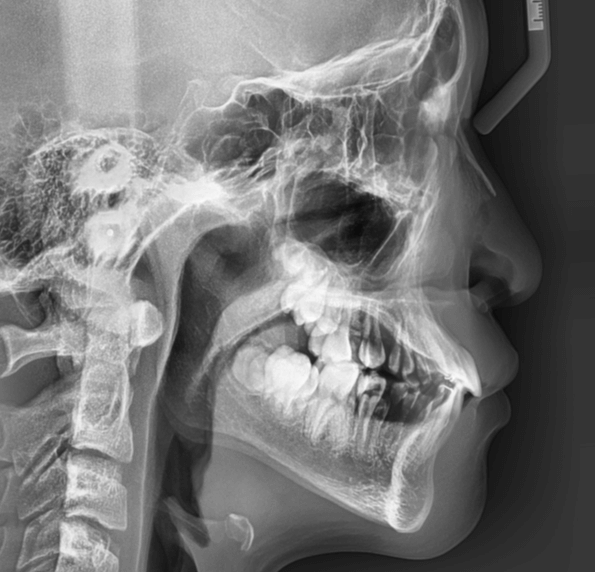

早期矯正治療 反対咬合症例②

主訴 | 前歯の噛み合わせが逆で、見た目や食事に違和感があることを心配されて来院されました。 |

診断結果 | 7歳8か月の男児 前歯の反対咬合診断 |

治療内容 |

|

治療後の経過 | 早期矯正治療は11歳5か月で終了し、現在は3〜4か月ごとの定期検診で経過観察中で、今後本格的な矯正治療へ移行予定です。 |

治療期間 | 3年6か月 |

治療費用 | 430,000円(税別) |